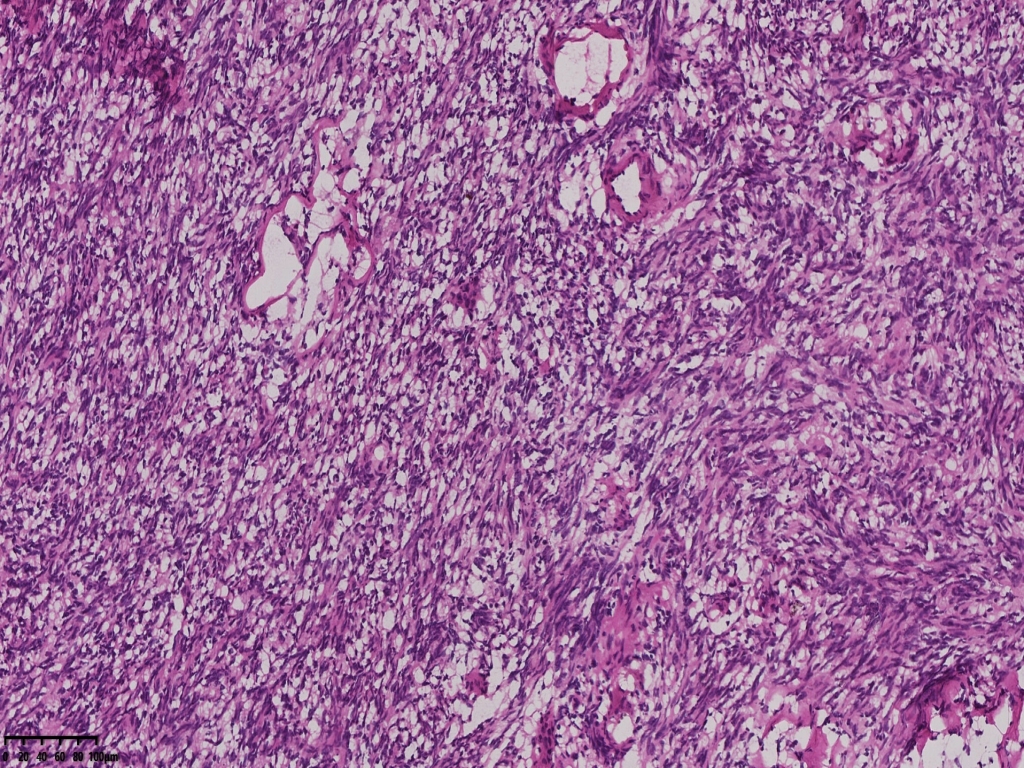

梭形

梭形细胞

冰冻切片取两块实性区组织,其中1块可见梭形细胞为主,另一块似上皮样细胞,细胞丰富密集。

术中考虑卵巢性索间质来源肿瘤,待石蜡及免疫组化。

考虑颗粒细胞瘤。